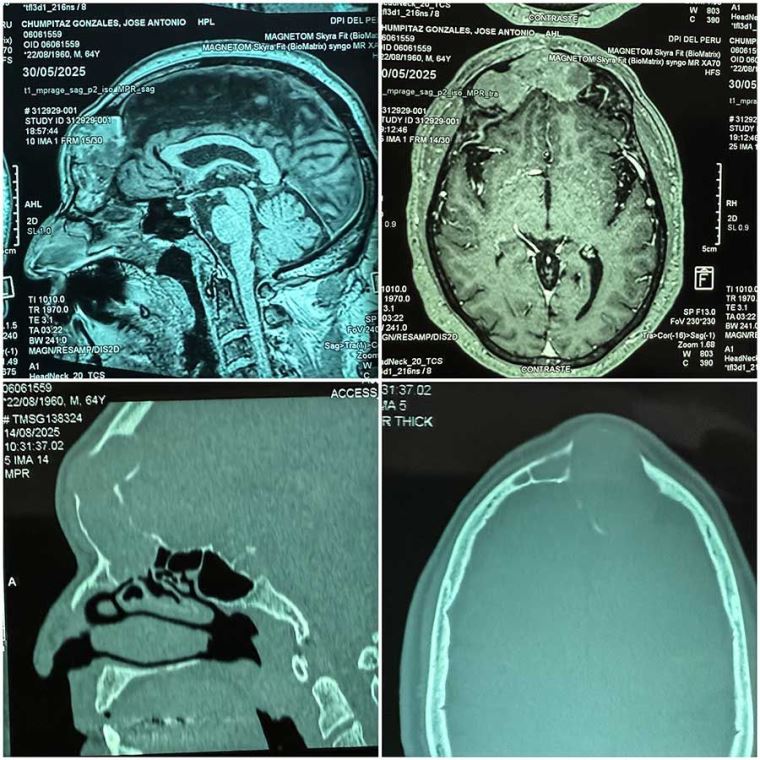

EsSalud: médicos del Sabogal extirpan tumor cerebral que comprometía visión del paciente

Compleja intervención quirúrgica tardó más de 10 horas, pero salvó la vida de don José Chumpitaz, que ahora mira el futuro con más esperanza junto a sus dos hijas.

El Dr. Mirek Marcos Quispe, cirujano plástico facial y otorrinolaringólogo del hospital Sabogal, explica que don José llegó con una tumoración en la frente que ya afectaba su movilidad y visión del ojo derecho.

“Realizamos un trabajo conjunto con el área de neurocirugía. Llevamos a cabo un abordaje endoscópico para la resección del tumor por vía intranasal”, detalla el especialista.

Agrega que la operación duró más de diez horas y aclara que este tipo de tumor no es común. “No es una tumoración frecuente. Son casos bastante aislados”, afirma. Sin embargo, asegura que el porcentaje de éxito en este tipo de intervenciones supera el 90 %. Actualmente, en el hospital realizan extirpaciones de tumoraciones de base de cráneo vía intranasal, sin cortes externos.